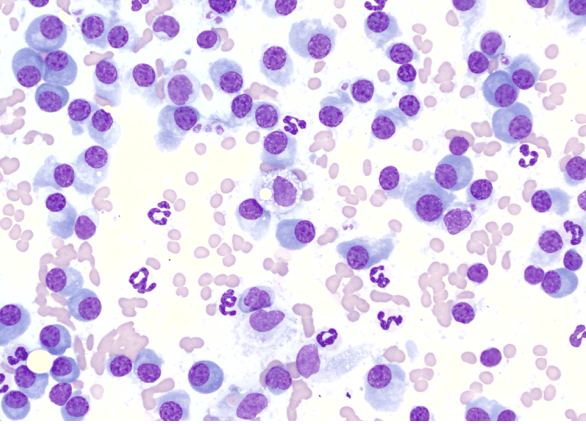

Cytologie de masse cutanée

Cytoponction d’une masse cutanée de 1,5cm sur le 3e doigt du membre thoracique gauche chez un Golden Retriever. Quel est votre diagnostic ? 1 – Un mastocytome 2 – Un plasmocytome 3 – Un histiocytome cutané bénin 4- Un lymphome cutané Si vous avez coché le choix 2, c’est la bonne réponse… Lire la suite